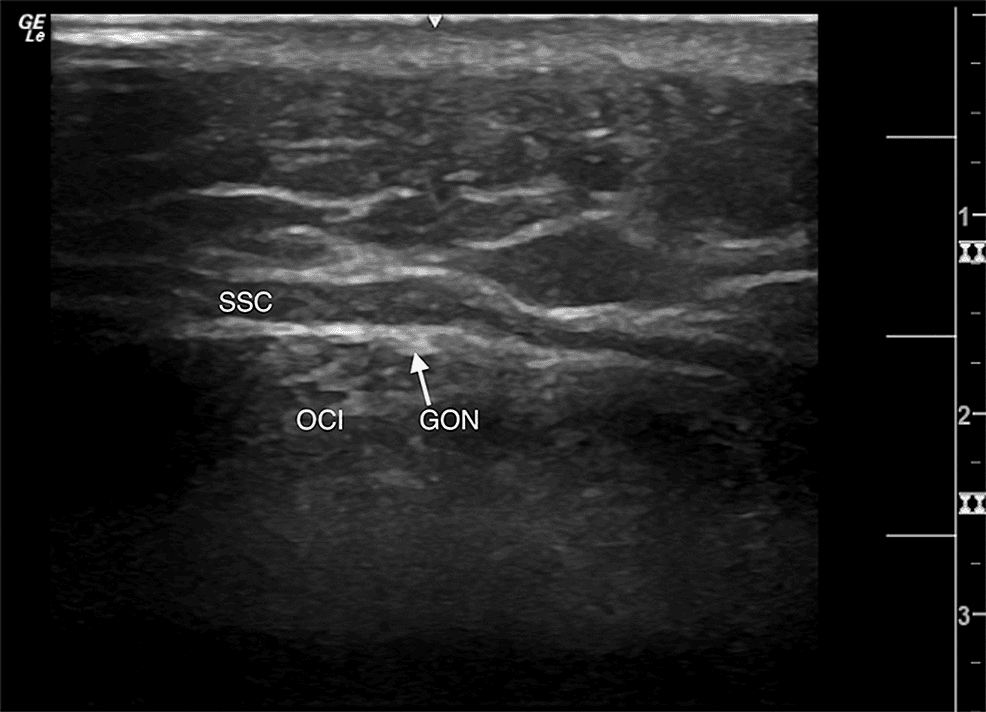

후두신경통 - 좌측 대후두신경(GON)의 고해상도 초음파 영상을 보여주는 사진입니다. 초음파 검사를 통해 대후두신경의 해부학적 위치와 주행 경로를 명확하게 시 Figure 1. 좌측 대후두신경(GON)의 고해상도 초음파 영상을 보여주는 사진입니다. 초음파 검사를 통해 대후두신경의 해부학적 위치와 주행 경로를 명확하게 시각화할 수 있음을 확인할 수 있습니다. 이는 후두부 두통이나 대후두신경통 환자의 진단 및 신경 차단술과 같은 치료적 시술에서 정확한 신경 위치 파악에 도움이 됩니다.

초음파 유도하에서 C2 횡돌기를 확인한 후, 고주파 선형 탐촉자를 사용하여 하두사근(obliquus capitis inferior)과 반극근(semispinalis capitis) 사이에서 대후두신경을 찾아 methylprednisolone 40mg 1ml와 0.5% bupivacaine 2ml를 주입했습니다.